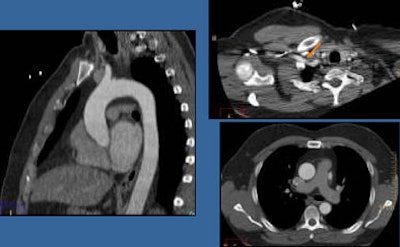

![]() |

| Helical and axial scanning techniques (above). According to the results for both methods (below), scan times and image quality are essentially the same, but radiation dose is dramatically lower when the axial scanning technique is used. All images courtesy of Sandra Halliburton, PhD. |